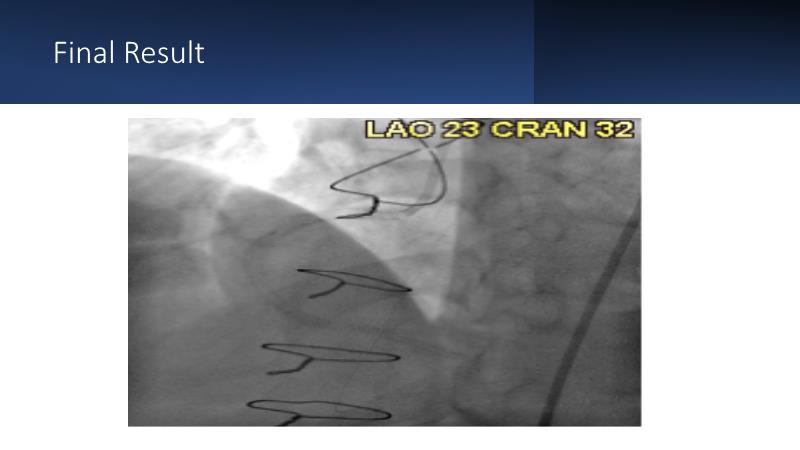

Next generation of DES technology, what it's all about? Find out in this session where experts will present complex cases from around the world and discuss the new indications for which they can be used.

• To know why and how a fusion coating of DES+DCB stent platform is effective for the treatment of cardiovascular disease in diabetes mellitus patients via case presentations

• To understand why you can count on customised drug delivery platform of DES+DCB in complex settings with imaging-based evidence through case presentations